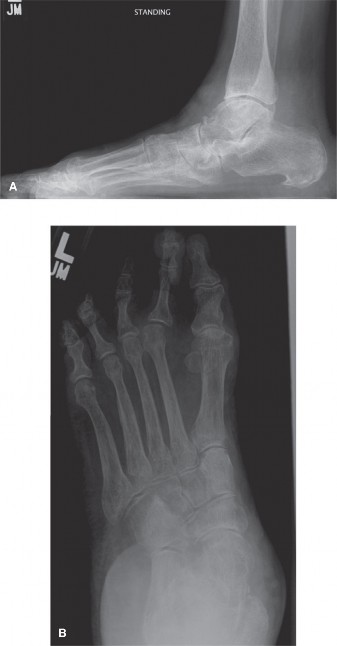

* Identifying deformities: Such as pes planus (flatfoot), pes cavus (high arch), hallux valgus, and other forefoot, midfoot, or hindfoot malalignments.

* Hallux valgus: Characterized by increased intermetatarsal angle (1-2), hallux valgus angle, and distal metatarsal articular angle.

Biomechanically, the foot and ankle function as a mobile adaptor and a rigid lever. Radiographs assist in understanding static deformities that compromise these functions. For instance, in pes planus, a decreased calcaneal pitch and talonavicular uncoverage contribute to a rigid flatfoot. In arthritis, loss of joint space alters load transmission and motion. Understanding these relationships is critical for surgical planning, whether the goal is fracture reduction, arthrodesis, or osteotomy to restore alignment.

* Adult Acquired Flatfoot Deformity (AAFD) with significant radiographic parameters: Talonavicular uncoverage, increased talar declination, hindfoot valgus.

2. Deformity Analysis: For reconstructive cases (e.g., flatfoot, hallux valgus), precise measurements from weight-bearing radiographs (e.g., Meary's angle, Talar-1st Metatarsal angle, calcaneal pitch, talonavicular coverage, Intermetatarsal angle, Hallux Valgus Angle) guide osteotomy planning and fusion angles.